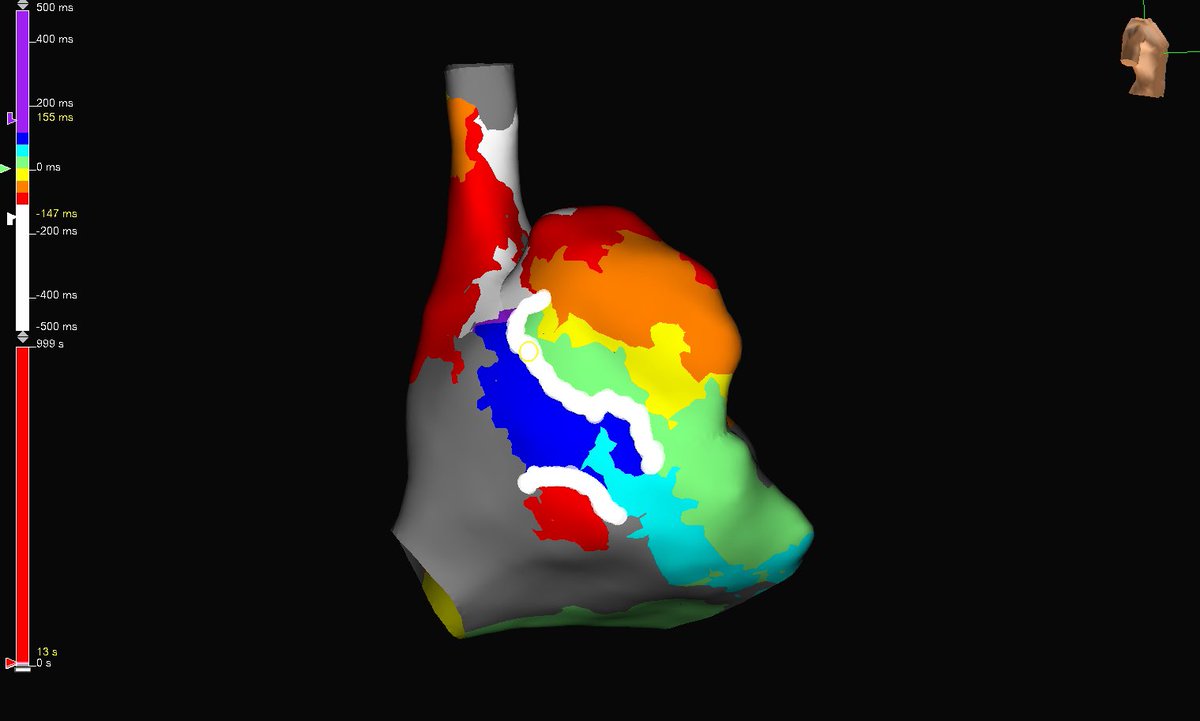

PLSVC is common; PLSVC w/o right SVC (isolated SVC) and a GIANT coronary sinus isn’t. This aneurysmal CS is like another cardiac chamber. Flutter termination in a patient with history of CABG. #mapmoreburnless #EPeeps #HDGrid #atypicalflutter #JustATypicalDayinEP @ArHeartHospital

MonicaYLo's tweet image. PLSVC is common; PLSVC w/o right SVC (isolated SVC) and a GIANT coronary sinus isn’t. This aneurysmal CS is like another cardiac chamber. Flutter termination in a patient with history of CABG. #mapmoreburnless #EPeeps #HDGrid #atypicalflutter #JustATypicalDayinEP @ArHeartHospital